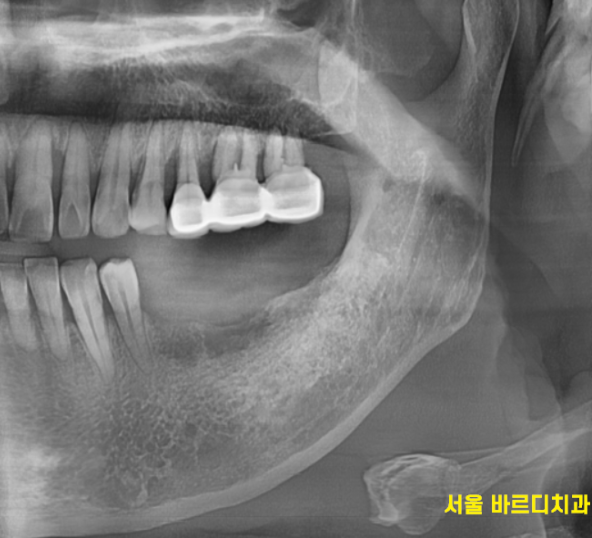

230707

겉으로 봤을 때는 잇몸만 느껴지지만

x-ray를 보실까요~?

230717

임플란트가 잘 심어져있습니다.